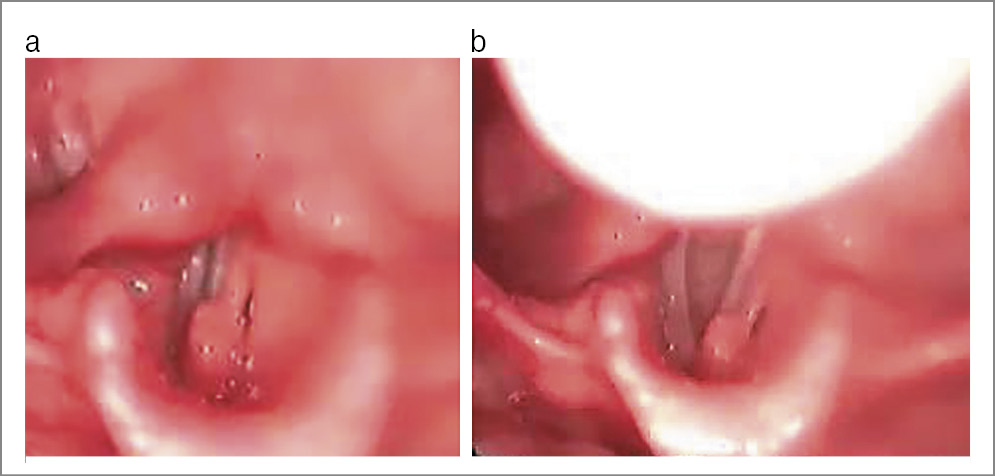

Исходя из клинико-эндоскопической картины гортани, нами выделены две степени дистопии. Первая степень диагностирована у 18 (22%) , а вторая – у 11 (13%) детей. Для дистопии 1-й степени характерны следующие проявления: в момент фонации черпаловидный и клиновидный хрящи одной половины гортани выступали в ее просвет, но не заходили за срединную линию. Черпало-надгортанная складка той же половины располагалась более перпендикулярно относительно голосовой щели, чем противоположная. В момент вдоха черпаловидные и клиновидные хрящи размещались симметрично относительно срединной линии гортани, при этом сохранялась некоторая асимметричность в расположении черпало-надгортанных складок (рис. 7).

Рис. 7. Девочка М., 8 лет. Дистопия черпаловидных хрящей 1-й степени, узелки голосовых складок: а – фонация; b – дыхание.

Для дистопии 2-й степени характерна иная картина. Во время фонации черпаловидный и клиновидный хрящи, выступающие в просвет гортани, заходили за ее срединную линию, и закрывали заднюю треть голосовых складок. При дыхании они располагались симметрично, однако сохранялась асимметрия черпало-надгортанных складок (рис. 8).

Рис. 8. Мальчик Ж., 17 лет. Дистопия черпаловидных хрящей 2-й степени, хронический ларингит: а – фонация; b – дыхание.

Дистопия черпаловидных хрящей проявилась не только их асимметричным расположением, но и изменением показателей вибраторного цикла. Колебания голосовых складок у всех пациентов имели асимметричный, нерегулярный характер. В силу перечисленных анатомических особенностей пациенты оказались вынуждены использовать форсированную фонацию, что приводило к изменениям голосовых складок: гипотонусу – у 10 (12%) человек, узелкам голосовых складок – у 8 (10%), хроническому ларингиту – у 5 (6%), ретенционной кисте голосовой складки – у 1 (1%).

Только у 5 (6%) пациентов голосовые складки оставались интактными. Перечисленные изменения голосовых складок являлись компенсаторно-приспособительными, так как способствовали их смыканию и облегчали фонацию.

Дистопию черпаловидных хрящей необходимо дифференцировать с анкилозом черпаловидного сустава, а в некоторых случаях – с параличом голосовой складки. Дифференциальным отличием дистопии от анкилоза являлась нормальная подвижность черпаловидного хряща во время дыхания, т.е. их симметричное расположение относительно срединной линии гортани.

При парезе голосовой складки так же, как и при анкилозе, черпаловидный хрящ неподвижен при дыхании и фонации, ротирован на стороне пареза, но в отличие от дистопии в момент вдоха он не менял своего положения.